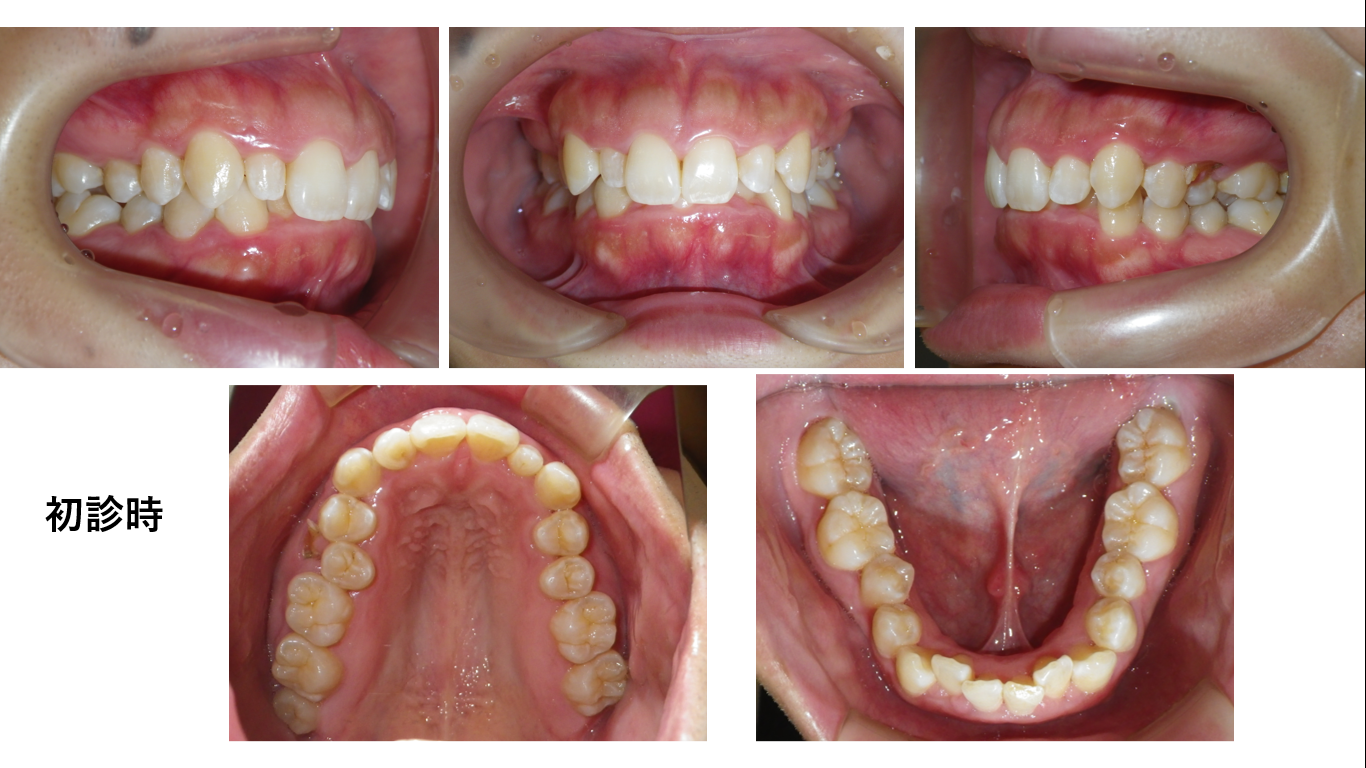

矯正症例143 AngleⅡ級2類

治療開始年齢24歳、治療期間3年、抜歯部位:下顎左右5番、上顎左右4番、治療費総額1,310,000(税込み)歯列矯正には以下のリスクを伴う場合があります。1最初は矯正装置による不快感、痛み等がありま...